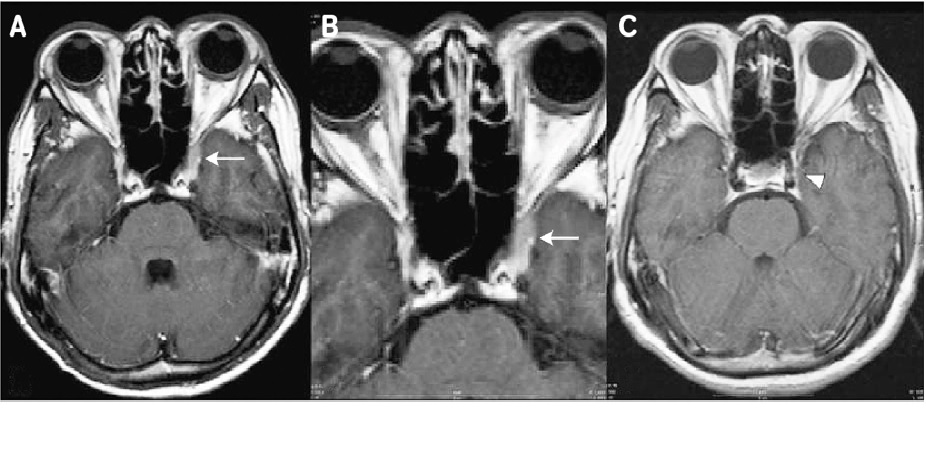

Hình ảnh Gadolinium-enhanced T1-weighted axial (A) và coronal (B) cho thấy một khối tăng cường liên quan đến xoang hang trái. Hình ảnh Gadolinium-enhanced T1-weighted axial (C) sáu tháng sau khi điều trị bằng steroid